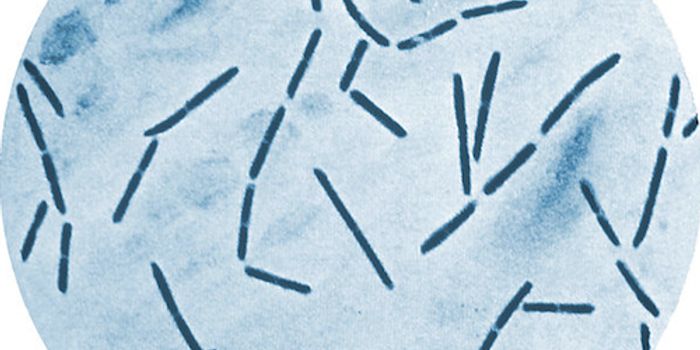

JUN 08, 2022Clinical & Molecular DXClostridium bacteria are a normal component of the gut microbiome. In rare cases, dysbiosis of Clostridium in the body c ...

OCT 17, 2021MicrobiologyThe world is full of microorganisms. Luckily, most pose no threat to us. But some harmless bacteria have the potential t ...